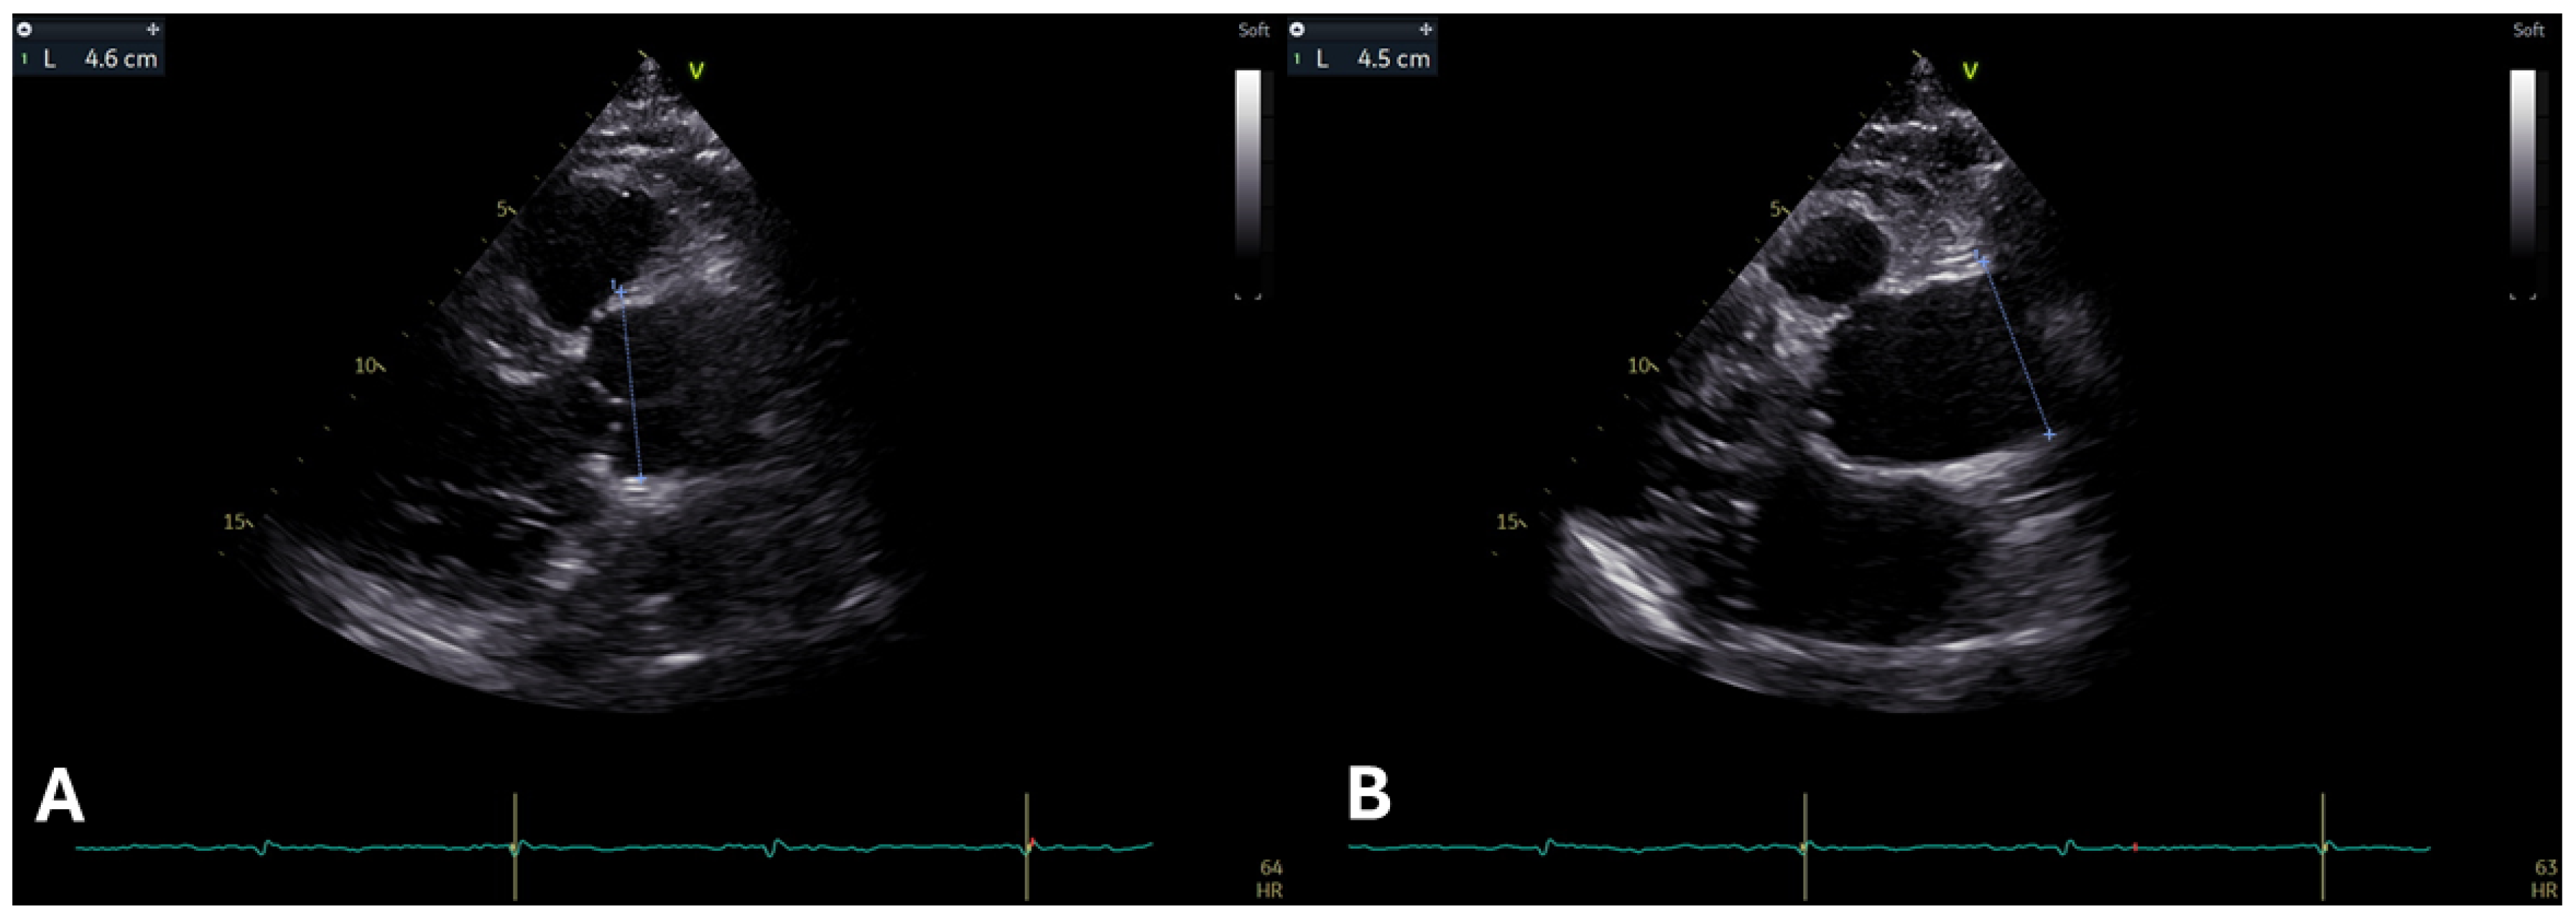

2.1. Aortic Root and Proximal Ascending Aorta Dilatation

| Echocardiography | Regularly evaluate aortic root and ascending aorta dimensions using standardized techniques (e.g., leading-edge-to-leading-edge in adults). Index measurements to body surface area and calculate Z-scores (≥2 indicates concern). Screen for mitral valve prolapse (MVP) and mitral annular disjunction (MAD) and monitor for complications like regurgitation. Include left and right ventricular function assessment, integrating strain imaging for early myocardial dysfunction detection. Monitor pulmonary artery dimensions, especially the root, for potential dilation. |